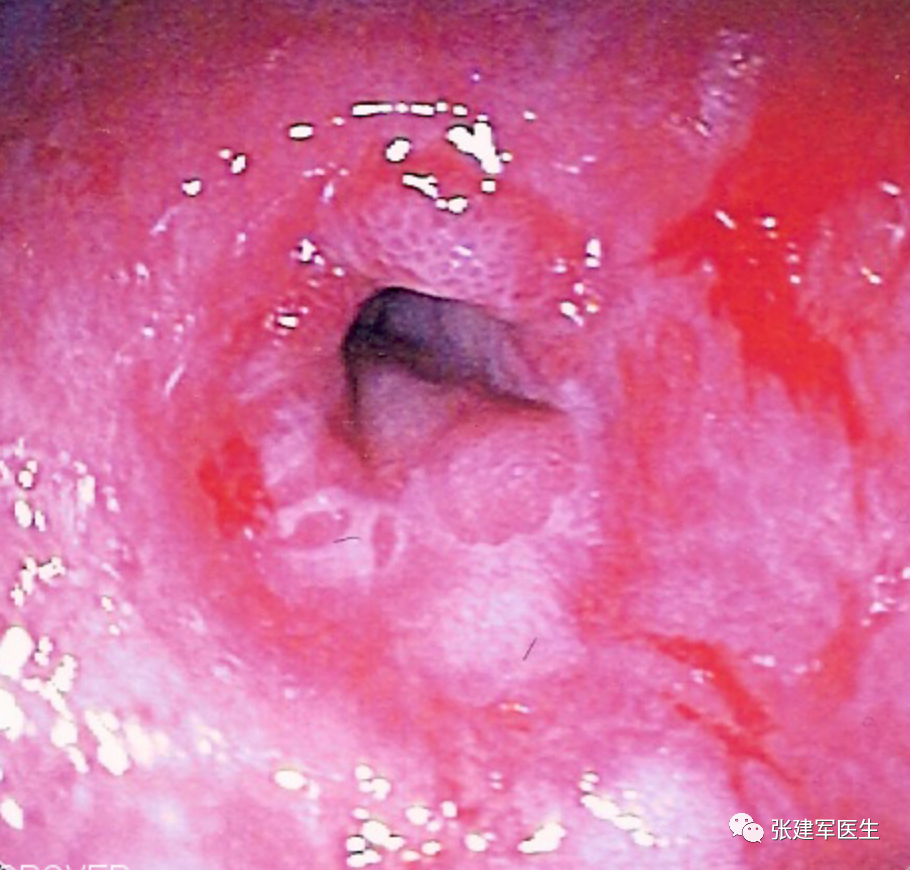

食道炎(Esophagitis),食道中的酸会导致食道内壁发炎。 慢性炎症会导致疼痛、吞咽问题、溃疡甚至出血。

巴雷特食管(Barrett's esophagus), 慢性炎症最终还会导致称为巴雷特食管的组织变化。 这种情况本身并无害,但被认为是癌前病变。

胃十二指肠镜检查

能直观评估食管、胃以及十二指肠粘膜状态,诊断糜烂性食管炎及巴雷特食管(Barrett's esophagus),明确食管裂孔疝的大小及类型,确定食管裂孔疝有无扭转。